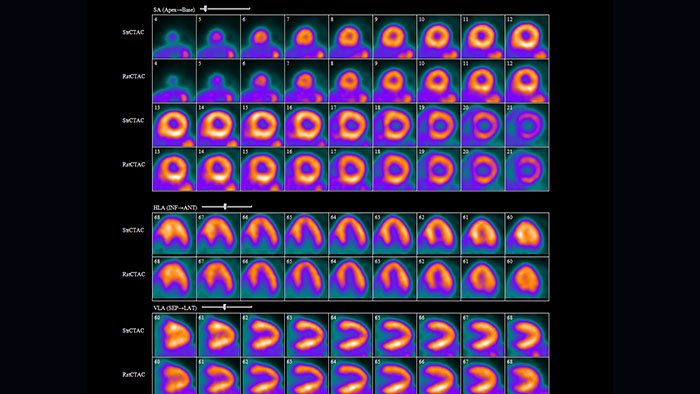

NM Cedars Sinai Cardiac Suite 2017*

Advanced cardiac quantification

Provides comprehensive cardiac quantification tools for gated, perfusion, and blood pool SPECT and quantitative PET. The Cedars-Sinai Cardiac Suite 2017 application provides efficient workflow for study interpretation with integration of perfusion and function.

Benefits

- Automated RV contouring, quantification and analysis.

- Manual perfusion polar map defect editor.

- User customizable viewing layouts.

- Enhanced Phase Analysis algorithm, Smart Launch, color pallet editor.

- QGS, QPS, QBP analysis.

- QPET analysis.

* Not available for sale in all countries. Please check for availability in specific countries.

NM Corridor4DM 2018*

SPECT and PET cardiovascular quantification, review, and reporting

Designed for advanced cardiovascular quantification and image display, and includes intelligent workflow and quality assurance measures for increased confidence. Quantifies myocardial perfusion, function, and viability using multiple review screens, with integrated reporting through customizable templates.

Benefits

- Quantifies, displays, and provides reporting for SPECT and PET myocardial perfusion and function, PET FDG metabolism, and SPECT blood pool studies in a single, configurable application.